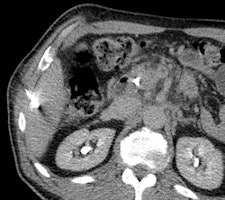

In nine cases -- eight soft-tissue, one liver -- MR fluoroscopy was used to define the entry site, and the physician used a fingertip or water-filled syringe as a marker. In 29 cases -- 11 soft-tissue, 18 liver -- a marker capsule (Adalat, Bayer) was affixed to the supposed entry side with adhesive tape, and the position was corrected after application of conventional sequences. After sterile draping, administration of local anesthesia and skin incision, an MR-compatible puncture needle (14-18 G) was placed subcutaneously outside the magnet.